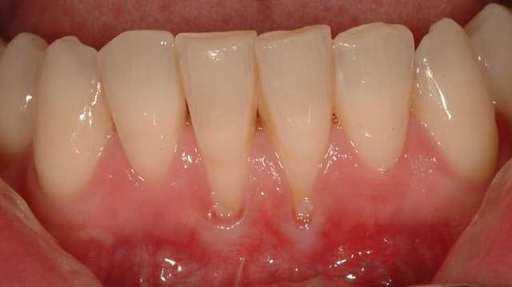

Receding gums occur when the gums move away from the teeth, exposing more of the tooth, including the roots. When this happens, gaps appear between the gums and the teeth. Bacteria can accumulate in these spaces, causing periodontal disease and tooth damage. In severe situations, the infection might begin to break down the bone beneath, resulting in tooth loss.

Gum recession occurs gradually, and many people are unaware that their gums are receding until it is too late. Gum recession symptoms include red or swollen gums, foul breath, oral sores, and pain or bleeding during brushing or flossing.